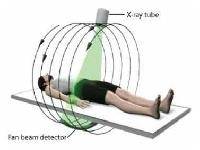

Мобильный рентгенаппарат + оцифровщик. Получение рентгеновского изображения на экране ноутбука. Вариант за 1,4 миллиона рублей под ключ.

Мобильный рентгенаппарат с печатью рентгенограмм на рентгеновской пленке. Цена 700000 рублей.